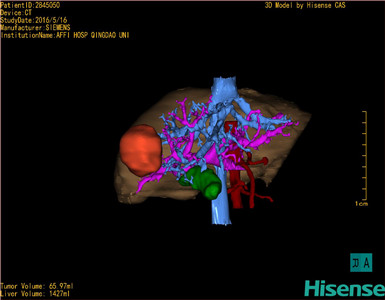

将0.625mm双源薄层CT资料的静脉期和动脉期Dicom格式文件导入海信CAS系统。

通过调节窗宽窗位调整CT序号,对肿瘤,肝实质,胆囊,下腔静脉,肿瘤,肝动脉、门静脉及肝静脉等进行三维重建;系统自动计算肿瘤体积和肝脏体积。

模拟手术操作,自动计算切除肿瘤体积。肝脏体积为1427ml,肿瘤体积为65.97ml,肿瘤体积为肝脏体积的4.6%,通过比对40-50岁正常肝脏体积为1368.38±279.24ml,通过术前模拟手术,精准判断切除后剩余肝脏体积能耐受,避免肝衰竭发生。

术前手术方案的规划。

术前三维重建:

重建图片